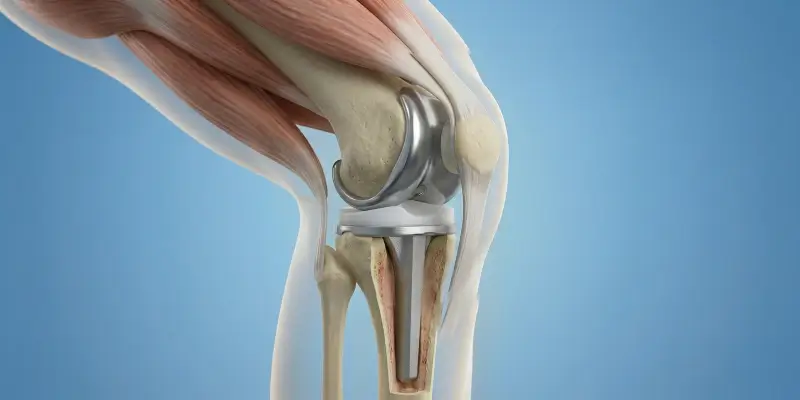

Total diz protezi, ileri osteoartrit ve diz hasarında hasarlı kıkırdak ve kemik yüzeylerinin metal ve polietilen protezle değiştirilmesidir. Endikasyonlar, cerrahi ve rehabilitasyon.